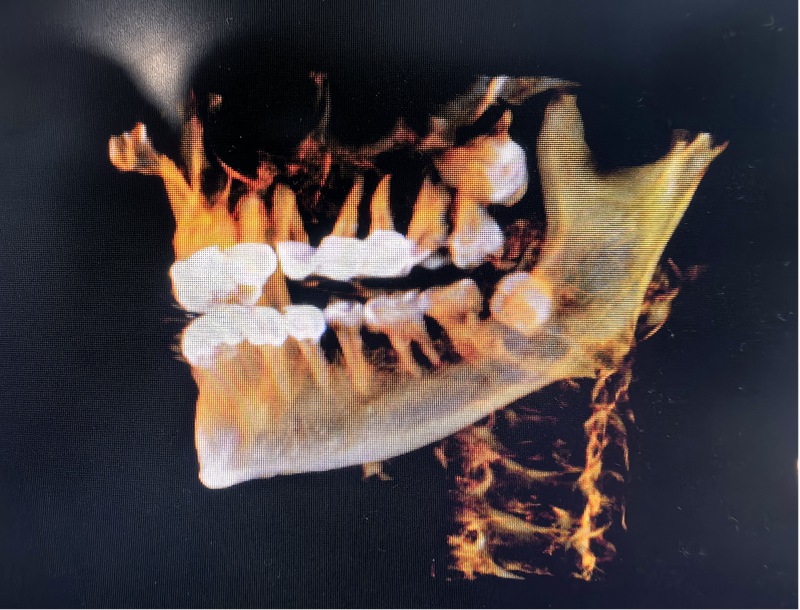

術(shù)中:精準(zhǔn)定位后利用超聲骨刀微創(chuàng)拔除。

然而,劉醫(yī)生憑借豐富經(jīng)驗(yàn)和精湛技術(shù),最終在門(mén)診順利完成這臺(tái)高難度手術(shù),纏繞謝女士多日的隱患被妥善解決。術(shù)后,她如釋重負(fù):“懸著的心終于能放下了!”這場(chǎng)看似簡(jiǎn)單的門(mén)診手術(shù),不僅消除了口腔健康隱患,更讓患者真切感受到專(zhuān)業(yè)醫(yī)療帶來(lái)的安心。

術(shù)后:鄰牙、神經(jīng)、鼻腔及上頜竇粘膜均無(wú)損傷。